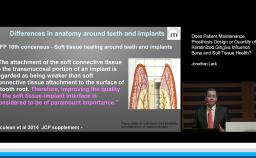

Despite these observations there are many who believe that peri-implantitis can not be compared to a "periodontal" disease adjacent to a dental implant. In fact, review of current literature that addresses this disease process would suggest that the management of this problem using similar technology for the management of periodontal disease may not be successful with implants.